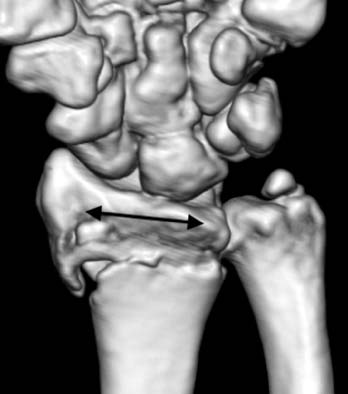

Fig. 6

The arrow indicates transverse ridge line of the distal radius.

jkfs-21-325-g006.jpg

Fig. 6 The arrow indicates transverse ridge line of the distal radius.